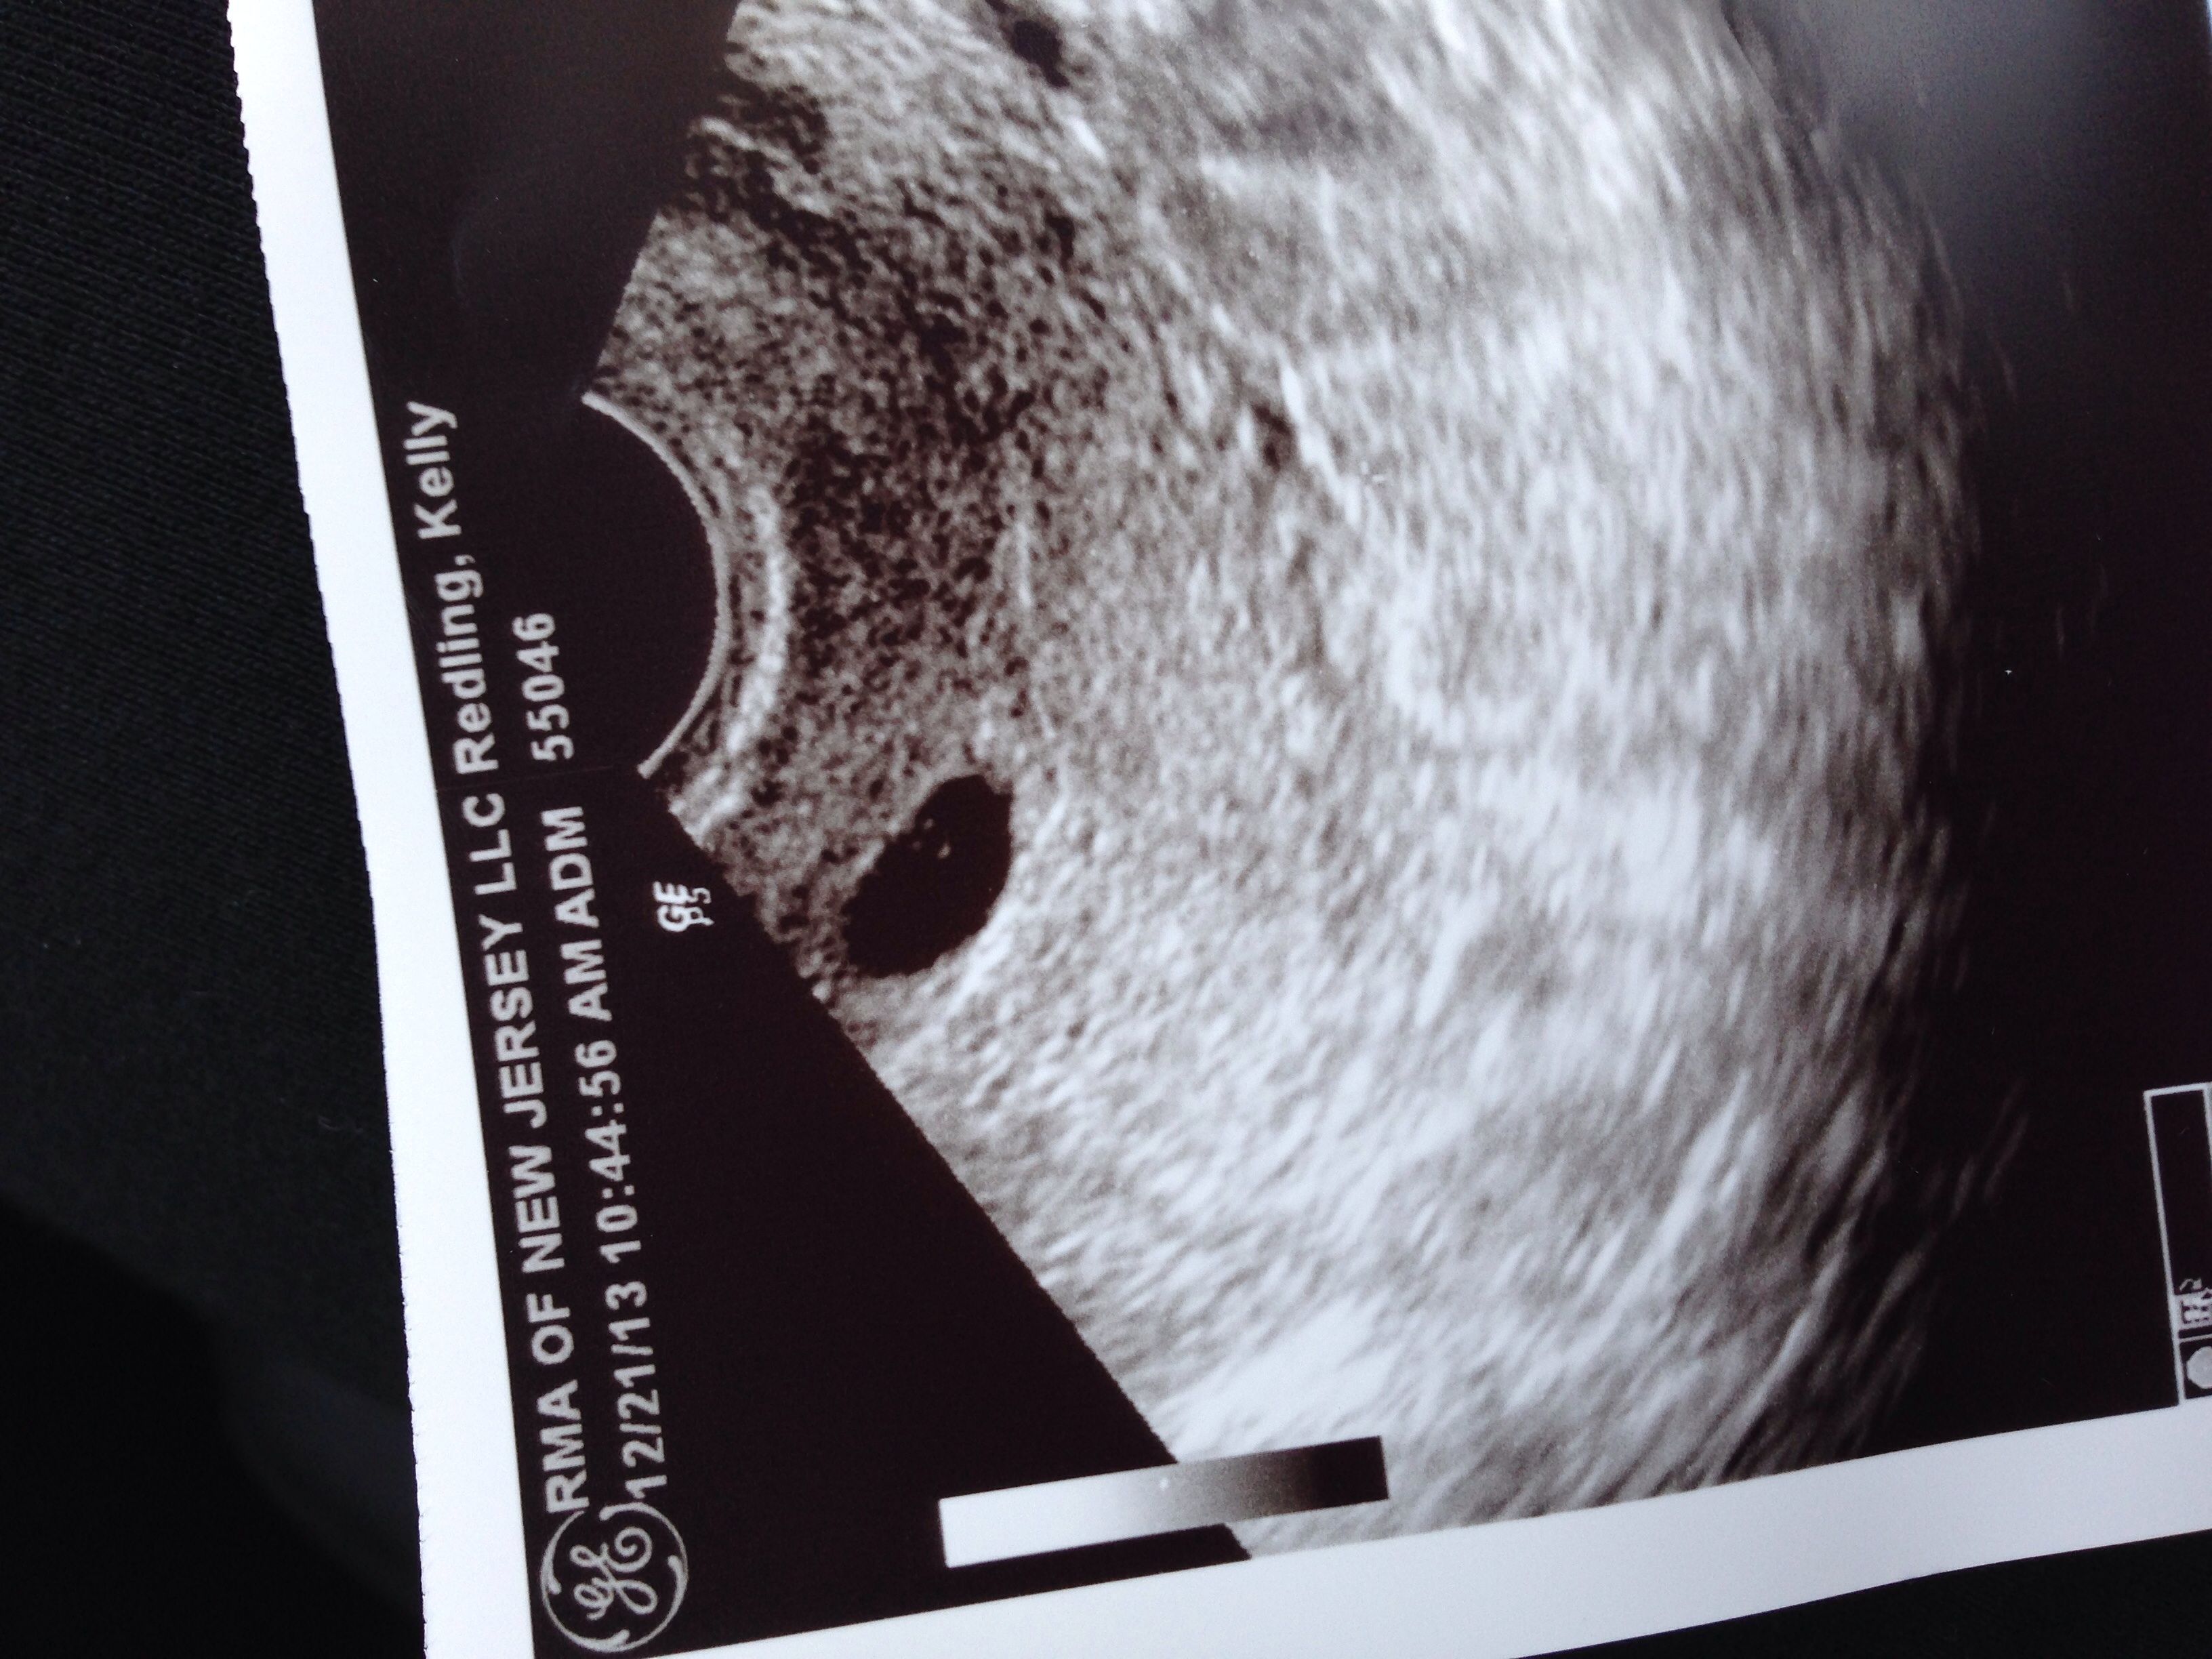

I guess it's time to move over to PAIF board again. I wanted to wait until our first ultrasound to make sure everything looked good. We saw 1 beautiful sac and yolk at 5w2d and doctor said everything looked great! Our beta came back today at 11,248! So looking good so far. Were so nervous to be too excited since we got through 2 ultrasounds and lost our LO last cycle at 8 weeks. So fingers crossed this is it for us! Ultrasound pic is attached! Weird seeing 3 dots don't know what that's about! He only pointed to the one dark one in the middle!